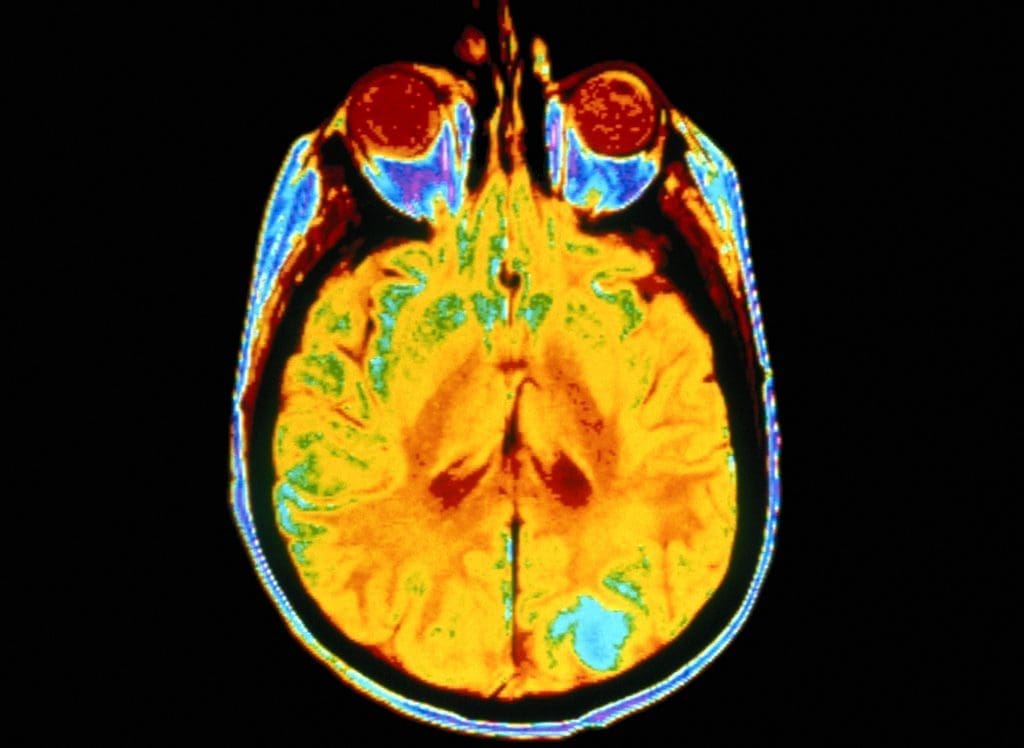

However, the researcher did find that a history of multiple hits to the head did significantly increase their risk of developing A.L.S. Men and women who sustained at least two concussions or other serious head injuries were much more likely to develop A.L.S. than individuals who have never experienced a concussion or severe blow to the head.

In the U.S., a few researchers have begun to look at football and A.L.S., given evidence that head trauma sustained playing football might contribute to neurodegenerative diseases. But to date, the football data has been inconclusive.